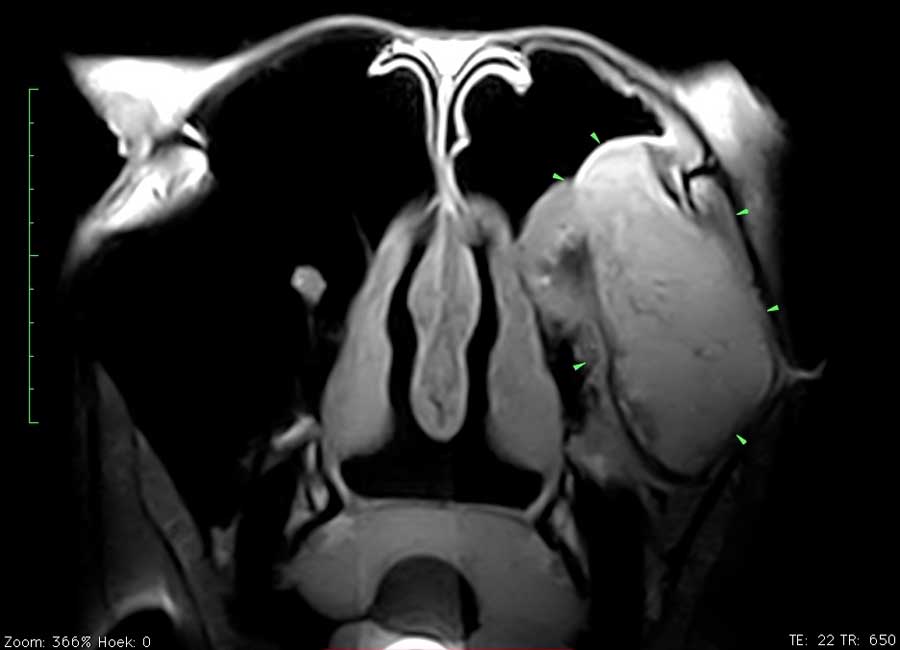

Dit paard had sinds enkele weken een unilaterale bloederige neusvloei. Op endoscopisch onderzoek was slechts een minimale afwijking ter hoogte van het linker ethmoid te zien. Bij radiografisch onderzoek was een grote massa in de sinus te zien. Er werd beslist een pre-operatieve MRI uit te voeren om de operatie te plannen en ook prognose beter te kunnen inschatten. Het ethmoid hematoom (PEH) bleek een groot deel van de linker sinus ingenomen te hebben.